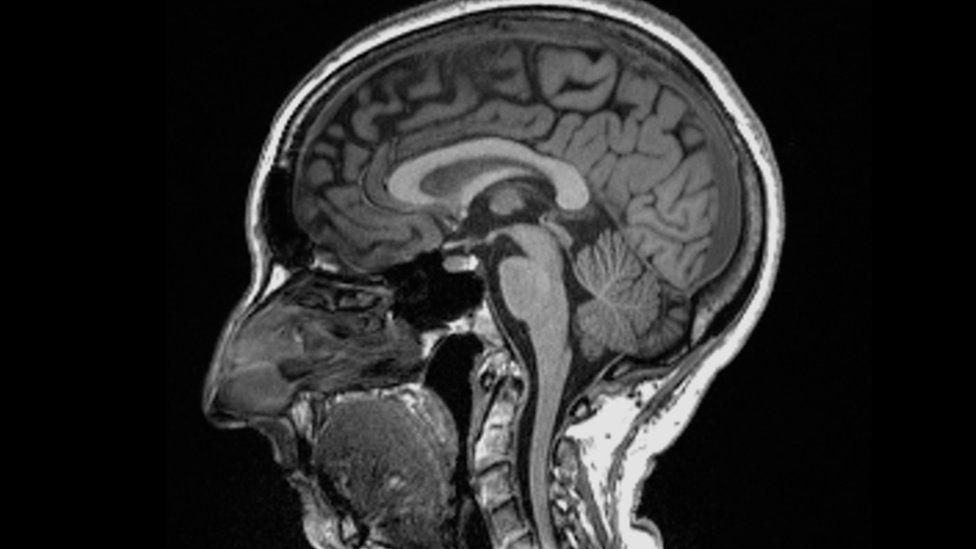

Scientists found significant differences in MRI (magnetic resonance imaging) scans before and after infection.

Even after a mild infection, the overall size of the brain had shrunk slightly, with less grey matter in the parts related to smell and memory.

The overall brain size in infected participants had shrunk between 0.2 and 2%

There were losses in grey matter in the olfactory areas, linked to smell, and regions linked to memory